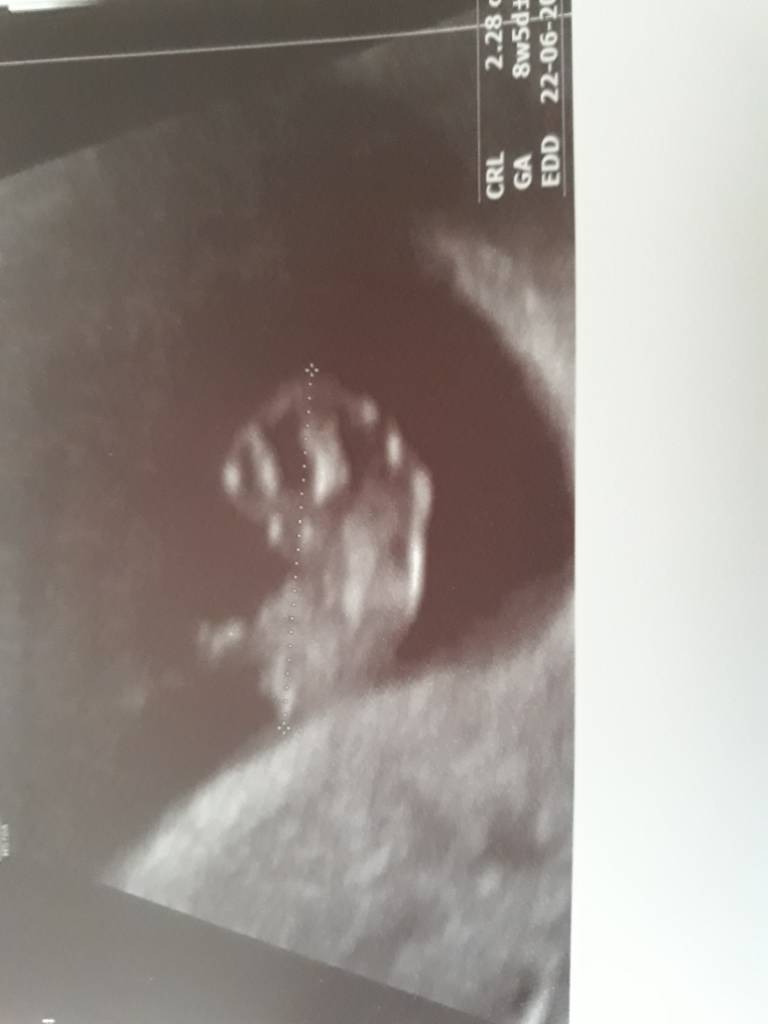

BoskoMiałam dziś wizytę chwale się moim kropkiem2.23cm stopa wystawiona do zdjęcia [emoji5] Zobacz załącznik 916716

super kropek:*Miałam dziś wizytę chwale się moim kropkiem2.28cm stopa wystawiona do zdjęcia [emoji5] Zobacz załącznik 916716

Super który tydzień?Miałam dziś wizytę chwale się moim kropkiem2.28cm stopa wystawiona do zdjęcia [emoji5] Zobacz załącznik 916716